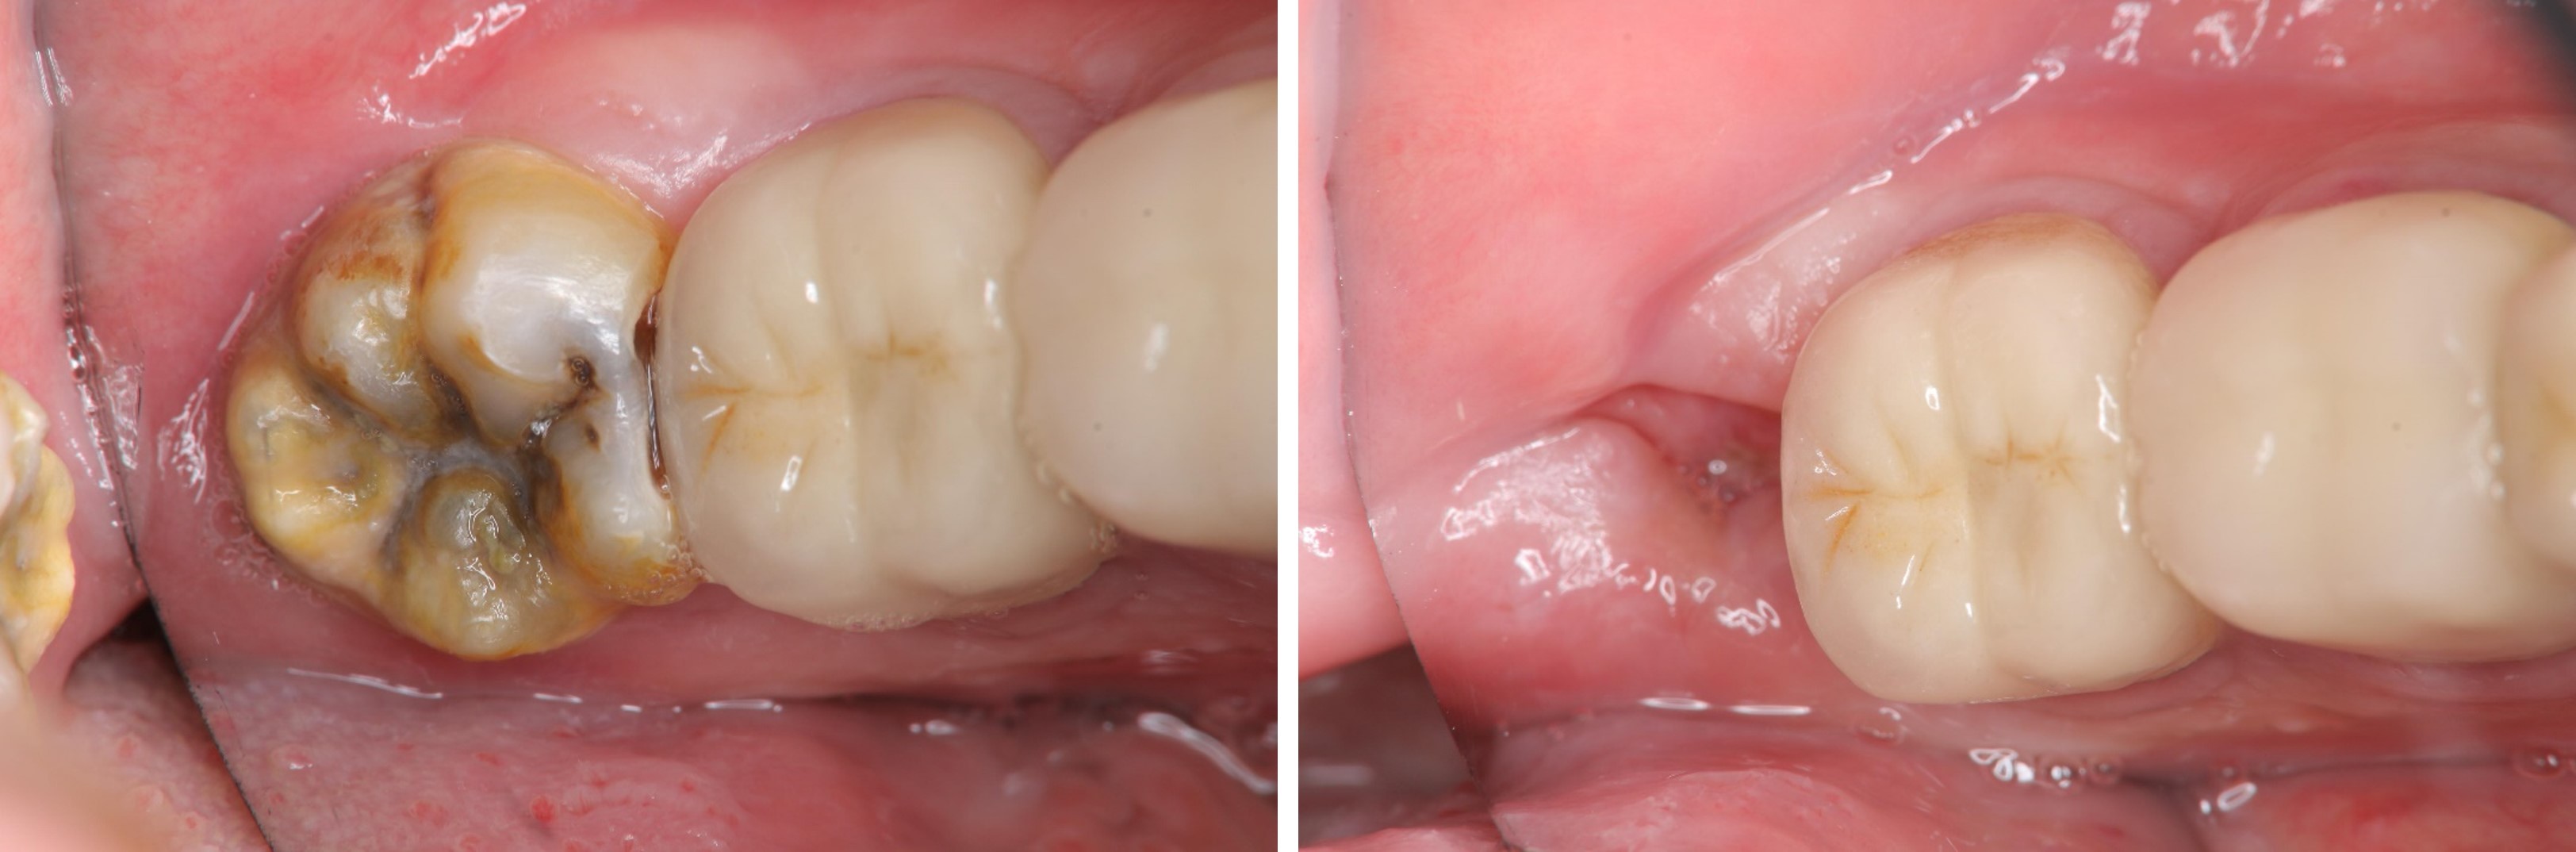

治療前,左下阻生齒深度蛀牙

術前、術後比較